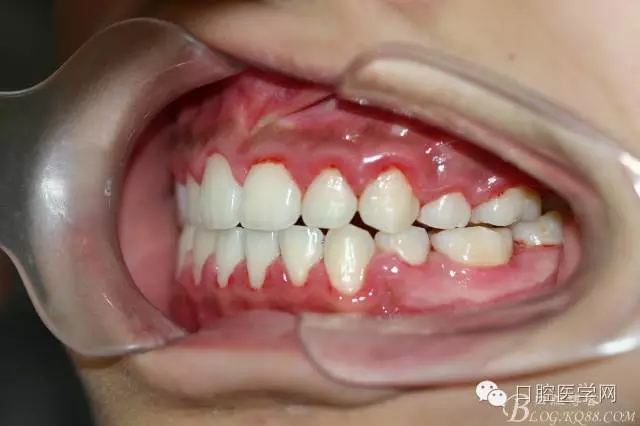

正畸查:替牙合。第一恒磨牙中性合。上牙弓尖圓型下牙弓方圓型。前牙覆合3度覆蓋7.5mm。下前牙咬到上舌側(cè)牙齦。上頜擁擠4.0mm,下頜擁擠

3.0mm。上頜稍前突下頜后縮,上下唇前突,上前牙覆蓋下唇,下唇外翻。面下三分之一過(guò)短,頦唇溝明顯,開(kāi)唇露齒,頦饜窩明顯。顳下頜關(guān)節(jié)開(kāi)閉口無(wú)彈響,無(wú)壓痛,開(kāi)口型開(kāi)口度正常。

正畸前照片: